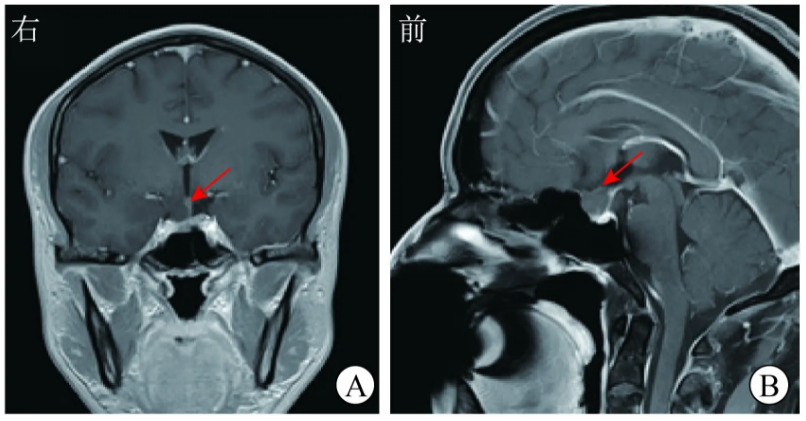

实验室检查:血常规、血生物化学(简称生化)指标,以及垂体相关激素[催乳素(PRL)、TSH、促肾上腺皮质激素(ACTH)、黄体生成素(LH)、卵泡刺激素(FSH)、生长激素(GH)、促黑素细胞激素(MSH)等)]水平均无异常。头颅CT平扫示:鞍上区偏右侧见一椭圆形稍高密度影,边界清晰,CT值为50~60 HU(图1)。

图1术前头颅CT平扫示,鞍上区偏右侧椭圆形稍高密度影(红色箭头所示)